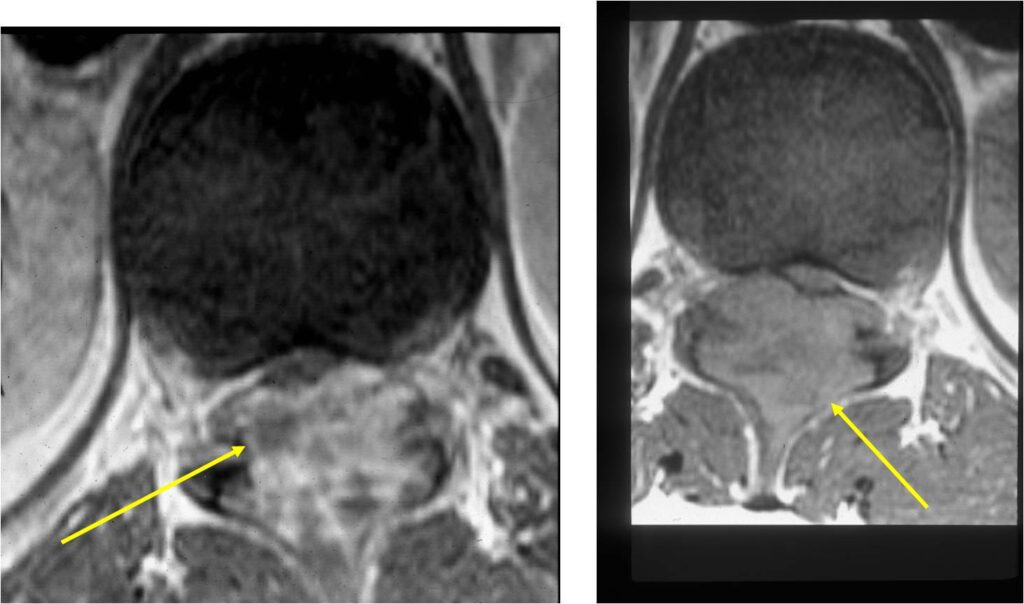

- Spine (40% of cases; usually posterior elements)

- Spinal lesions may be accompanied by muscle spasms, scoliosis and neurological manifestations

MRI:

- Also useful in determining extent

- There is often extensive edema around the tumor in the surrounding bone and soft tissues that can lead to a misdiagnosis of a malignant tumor.